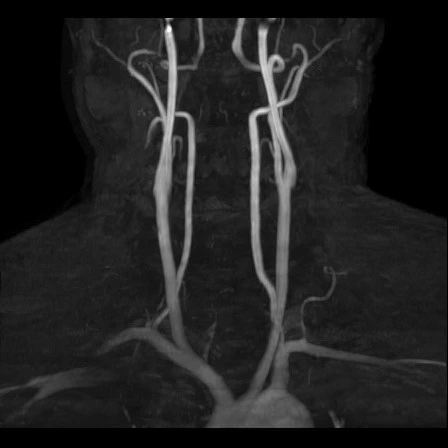

carotid MRA (e) : 목의 경동맥 혈관 상태 평가 (뇌로 가는 혈류 확인)

Carotid MRA (좌우 경동맥 자기공명혈관촬영)

영상을 보면.. 위에서, 옆에서, 밑에서.. 여러 각도에서 입체적으로 찍었어요.

3D로 뇌혈관, 심장으로부터 목으로 연결되는 경동맥도 잘 보이고,

내 뇌 구조가 이렇게 생겼구나! 정말 신기하더라고요!!

혈관 모습도 좌우 다 다르고 (당연한거지만 신기해서)

Brain MRA (Magnetic Resonance Angiography) : 뇌혈관 자기공명영상. 뇌 속 혈관이 좁아졌거나 막혔는지, 이상 혈관이 있는지 보는 검사.

Carotid MRA (e) : 좌우 경동맥 자기공명혈관촬영을 의미하며, 목의 주요 혈관 상태를 확인해서 뇌로 가느 혈류가 막히거나 좁아진 곳이 없는지 보는 검사. 필요하면 조영제를 사용해 혈관 상태를 더 선명하게 보는 검사.